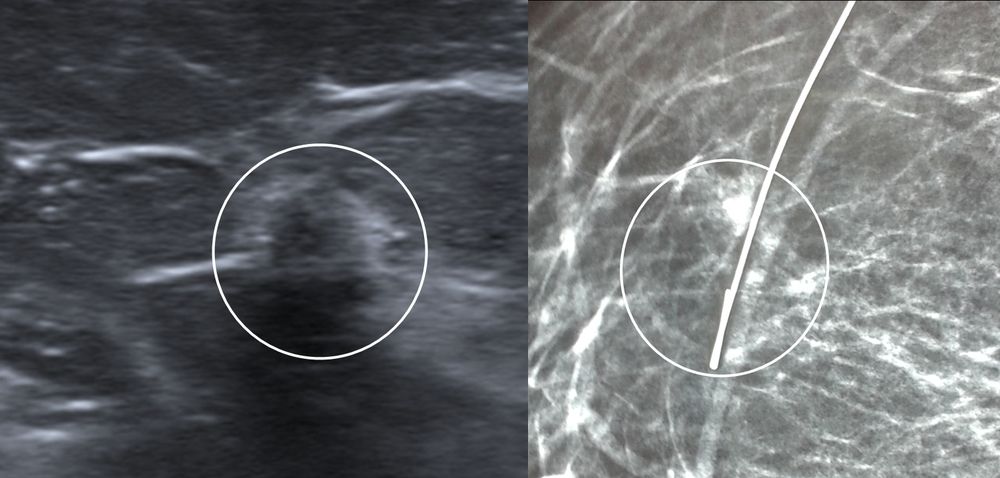

Σε περίπτωση που απαιτείται η χειρουργική αφαίρεση ενός ευρήματος που δε ψηλαφάται από το χειρουργό, τότε γίνεται η τοποθέτηση αγκίστρου σήμανσης (hook) λίγο πριν το χειρουργείο. Το άγκιστρο έχει σκοπό να καθοδηγήσει το χειρουργό για την αφαίρεση του σωστού τμήματος του μαστού, ώστε να αφαιρεθεί με ασφάλεια η ύποπτη βλάβη χωρίς να επηρεασθεί η αισθητική εικόνα του μαστού, πράγμα πολύ σπουδαίο ειδικά σε νέες γυναίκες και σε γυναίκες με μικρό μαστό.